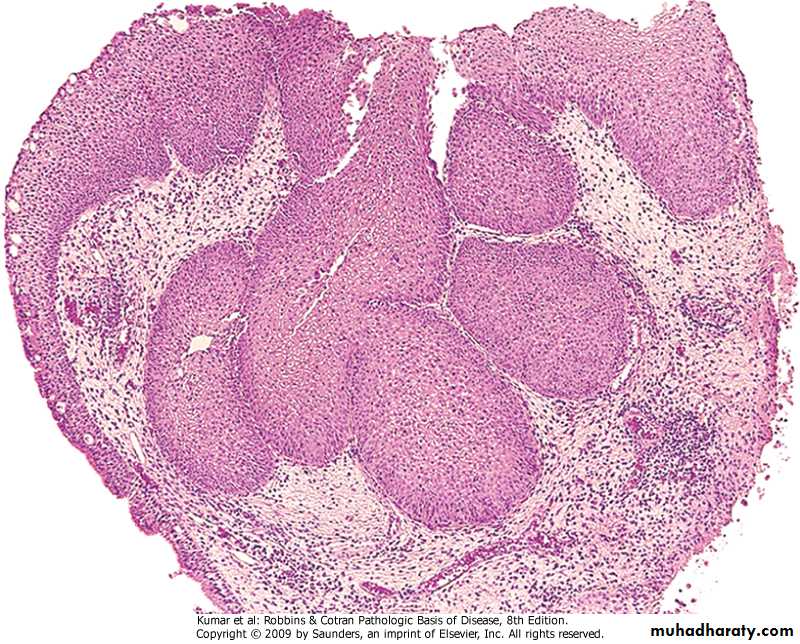

Bronchopneumonia

Patchy consolidation centered around inflamed bronchi & bronchiole. Multifocal & may be bilateral.Predisposing factors:

Pathology of Bronchopneumonia

Gross: Lesions are multiple & may be bilateral, affect basal segments of lower lobes.Micro: Acute inflammation of bronchi ,extend to involve surrounding alveoli which become consolidated. May involve the pleura